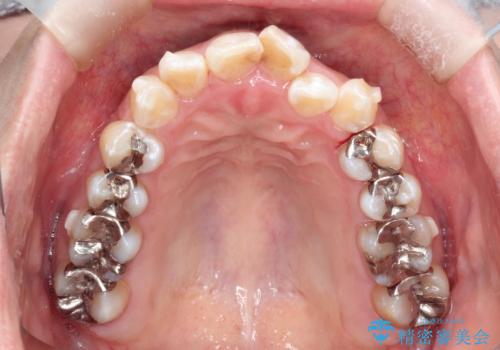

- 前歯のガタツキが気になると来院されました。

奥歯の噛み合わせは綺麗に噛んでいたため、前歯の叢生(でこぼこ)に集中して治療するように計画しました。

奥歯の噛み合わせは整っていたため、前歯の並びを美しく修正することに専念できました。

前歯のガタツキを改善する治療法として、マウスピース矯正が適していることが多いです。